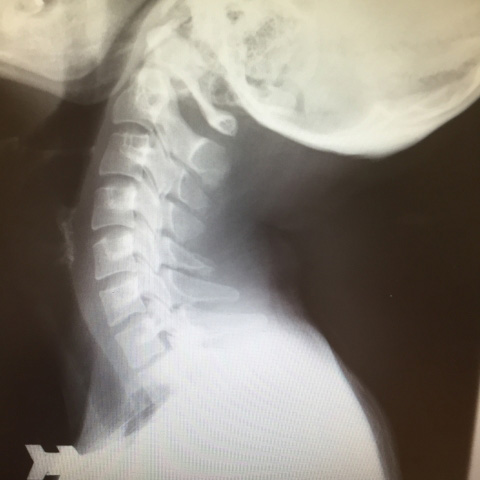

- 首の筋肉や靭帯だけが損傷を負っている「頚椎捻挫型」

- 神経根に損傷が及んでいる「神経根症状型」

- 脊椎にまで損傷が及んでいる「脊椎症状型」

このときに首が後ろに強くのけ反って曲がった状態(過伸展)になり、次に反動で頭部が前に倒れ、首が前方に強く曲がる(過屈曲)ことで、頸部の靱帯や筋肉などを痛めてしまうことを鞭がしなるように見えるのでむち打ち損傷といいます。

正式には、外傷性頸部症候群(がいしょうせいけいぶしょうこうぐん)・頚椎捻挫(けいついねんざ)という診断名になります。